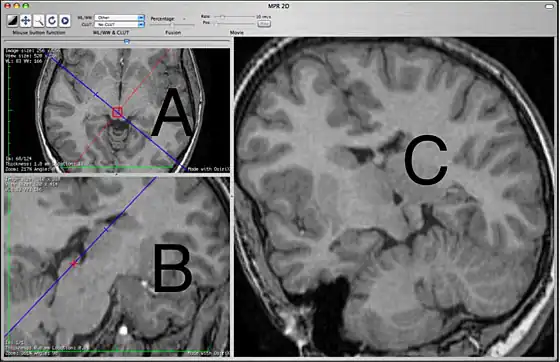

The 2D MPR window

This 2D MPR Viewer allows generating a MPR slice in any position and orientation through the 3D volume. This mode shows three viewing ports. In the picture above, the two on the left are labeled A and B. The third, on the right, is labeled C.

The primary purpose of the A and B view ports is to specify the plane that will be shown in the C view port. The A and B view ports are partially obscured by lines used specify the plane to be seen in C. These lines cannot be hidden. In this sense, the C view port is designed for diagnostic viewing and the other two view ports are primarily to specify what is to be shown in C. The view ports are not all equal, which may be different from what users of other MPR interfaces are expecting. View port A shows a blue line which corresponds to the orientation of what is being seen in C and also contains a red line that corresponds to what is seen in B. View port B shows only a blue line that also corresponds to what is seen in C. View port C has no lines.

The specifying view port A will show the original images in the plane that they were originally acquired, most commonly the axial plane. You can scroll through these images to choose the one that you want to work off. The specifying view port B shows planes that are orthogonal to view port A. If A is showing an axial image then on initially opening the 2D MPR Viewer, B will show a sagittal image. The specific orthogonal plane that is being created in B is indicated in the A view port as a red line. Under these initial circumstances, C will be showing a coronal reconstruction that corresponds to the blue line.